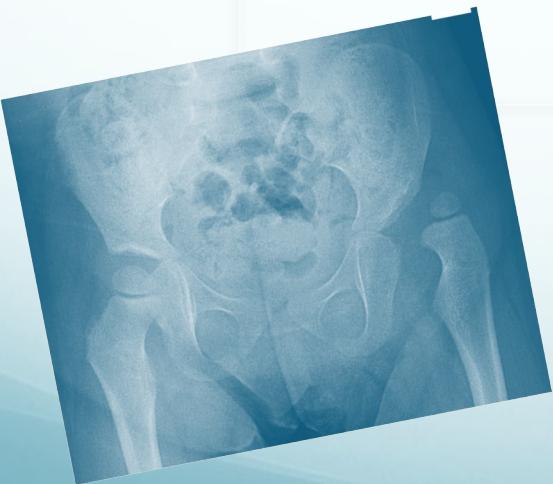

Common Congenital Lower Limb Problems encompass two major conditions:

- Developmental Dysplasia of the Hip (DDH) - A spectrum disorder affecting hip joint development